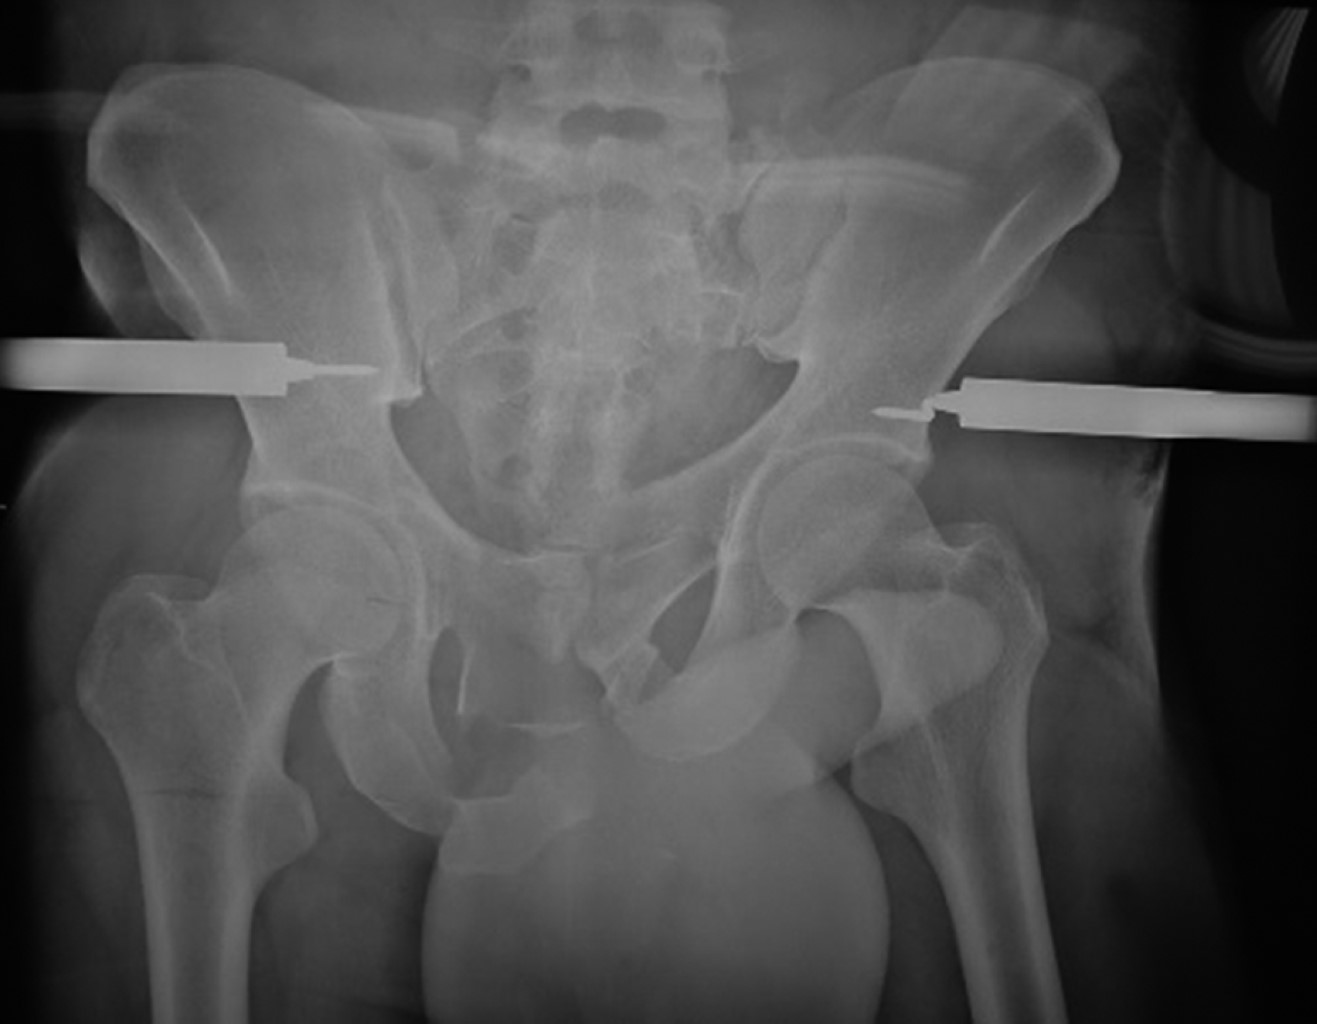

Se colocan compresas o un campo en la región anterior de los muslos y del abdomen para evitar el choque directo del clamp y evitar lesiones por presión (Figura 5). No debe movilizarse o levantar al paciente del clamp, situación que es común por la falta de conocimiento del personal paramédico a cargo del paciente. Se realiza una radiografía de control en proyección anteroposterior de la pelvis para verificar la posición de los clavos y la reducción de la lesión (Figura 6).